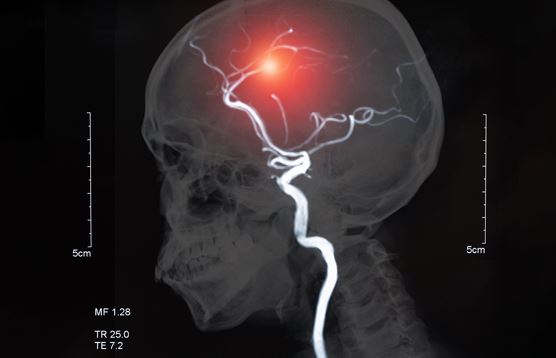

아무튼 뇌졸중은 뇌의 혈관이 좁아지고 해당 혈관에 피가 지속적으로 지나가면서 혈관이 무리를 하여 터져버리는 증상이다. 평균 5시간 이내에 병원에서 치료를 받지 못하면 사망에 이를 수 있는 무시무시한 질병이다.

뇌를 주기적으로 정밀검사를 하기 위해서는 MRI 촬영을 정기적으로 받아야 한다, 허나 서민의 입장에서 과연 정기적으로 MRI 검사비용을 감당할 수 있을까?

그렇다면 어떻게 우리 뇌를 안전하게 지키고 뇌졸중으로 부터 예방할 수 있을까? 바로 MRI를 보험처리 받는 방법인데,